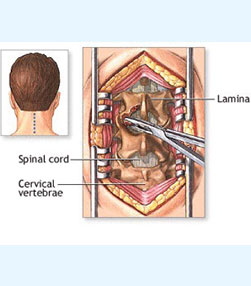

- Spine surgery - More than 3000 spinal surgeries including 40 spinal tumors microdiscectomy, MIS TLIF, artificial disc replacements, multilevel corpectomy, CV junction stabilization.